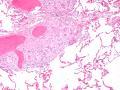

星状小体结节病

显微镜下显示出肺内结节病性肉芽肿,包含星状小体,使用HE染色